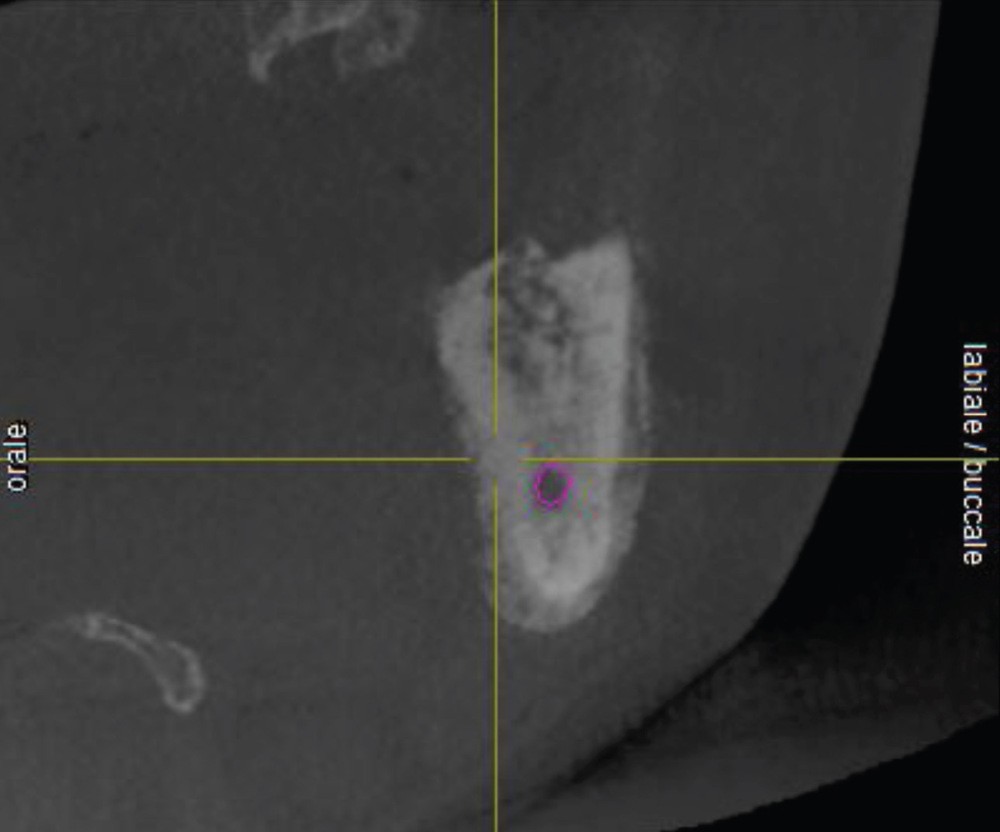

L’examen radiologique (scanner ou tomographie a faisceau conique) est très évocateur. Il montre un épaississement périosté avec « aspect mixte » de l’os médullaire et des « perforations corticales ».

L’ostéomyélite passe par plusieurs stades au cours de son évolution. Au début, les zones d’ostéolyse et de sclérose sont invisibles radiologiquement…